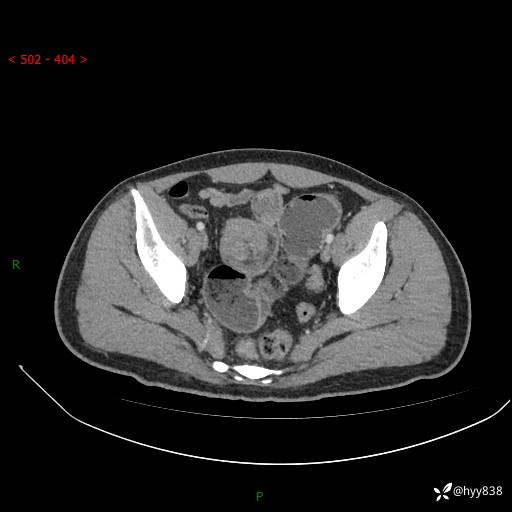

年轻男性,腹痛5月余。除了肠梗阻,你还能看到什么---结果公布~

现病史:患者于5月前无明显诱因开始出现腹痛,上明显,为间断性胀痛不适,无畏寒发热,无心慌气促等特殊不适,遂来我院。我院门诊遂以“腹痛原因待查”收入我科。 起病以来,患者精神、饮食、睡眠欠佳,大小便正常。体力体重无明显变化。

腹部CT增强扫描(动脉期+静脉期)